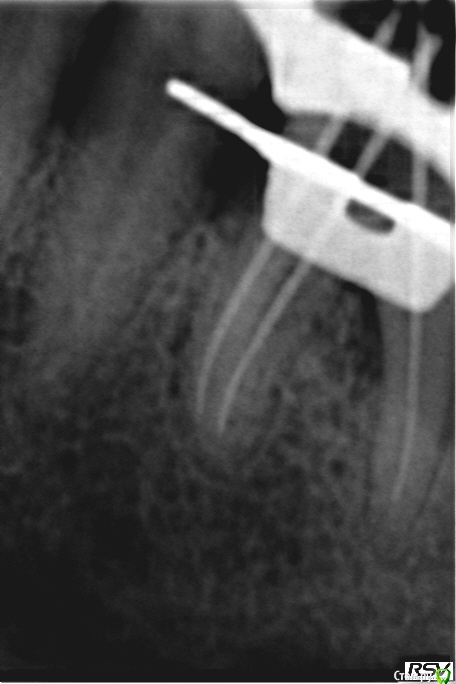

Ирина Игоревна Опубликовано 11 марта, 2015 Автор Поделиться Опубликовано 11 марта, 2015 Оптг бы глянуть и снимки до леченияДо лечения снимок к сожалению не делали,вечером могу скинуть снимок с инструментами в 1посещение Ссылка на комментарий

Ирина Игоревна Опубликовано 11 марта, 2015 Автор Поделиться Опубликовано 11 марта, 2015 с мастер штифтами в 1 посещение,дистальный потом доработала Ссылка на комментарий